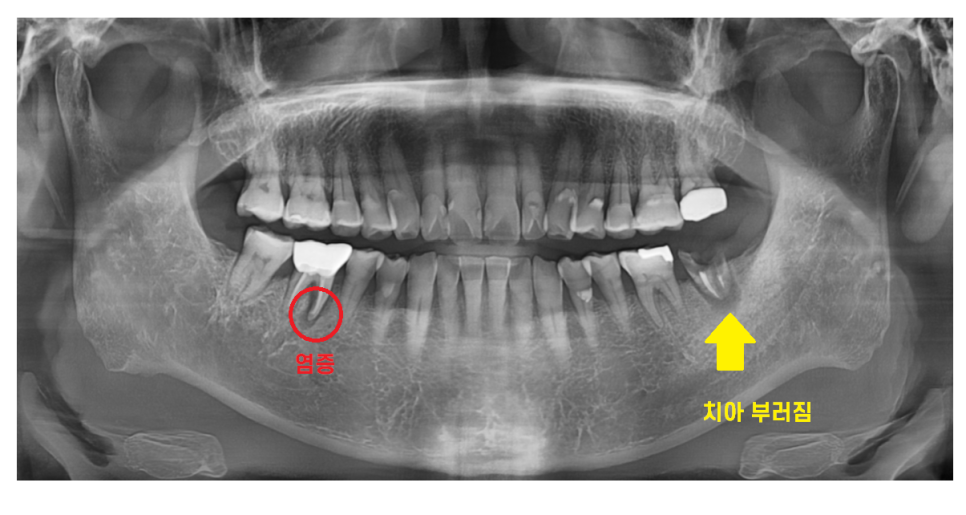

230130

왼쪽 아래 치아가 너무 아파서

도저히 못참겠다고 하셨습니다.

부러진지는 한참 됐는데

진통제를 먹으면서 참으셨답니다.

부러진 부위는

까맣게 변했을정도로 상태가 안좋았습니다.

외관상의 문제보다

뿌러지고 방치 되면서

치아 주변 뼈가 녹은게 관찰됩니다.

통증이 있는 상태라

해결을 위해서는 치아를 뽑아야 했는데요.

230214

아프지는 않다고 하셨지만

오른쪽 아래 어금니 치아도 염증이 있었습니다.

231029

이미 잇몸 밖으로 여드름 마냥

고름이 나오고 있었거든요ㅠㅠ